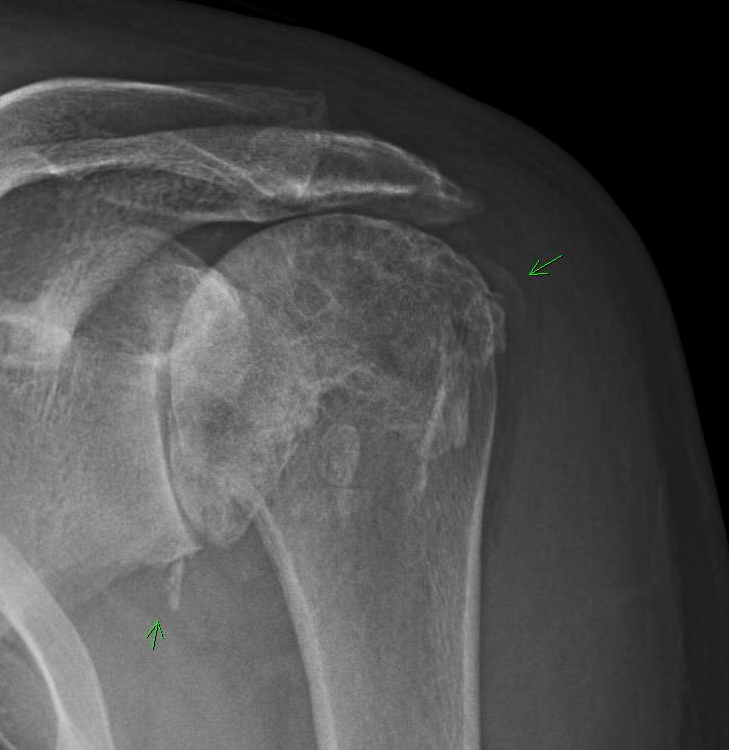

From shoulderarthritis.blogspot.com

UW Shoulder and Elbow Academy Shoulder arthritis and complete cuff deficiency the CTA prosthesis Arthritis Deficiency Of Osteoarthritis is a degenerative joint disease that primarily impacts the cartilage in your joints. Osteoarthritis has often been referred to as a wear and tear disease. It happens when the cartilage that lines your joints is worn down or damaged and your. Vitamins and minerals play a critical role in staying healthy, but getting enough of certain nutrients is even. Arthritis Deficiency Of.